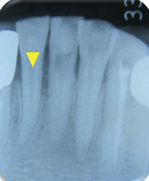

症例(マイクロスコープを用いた歯の根の治療:破折ファイルの除去)